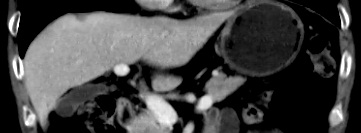

03-03复查CEA、CA199降至正常范围,胸腹部CT提示胃壁变薄,肝脏病灶及多发淋巴结较前均明显缩小,营养状况改善,3月内体重增加7.5%,PG-SGA评级再次恢复为B级。

03-04至08-11 “曲妥珠单抗+白蛋白结合型紫杉醇+替吉奥”方案治疗7周期。05-06胸腹部CT扫描:肝脏病灶较03-03老片缩小,评估病情SD。期间出现I°白细胞减少,低钾血症,一过性心功能下降,对症处理后好转。目前一般状况评分0-1分,近3月体重较3月前增加7%。

二线治疗再次有效